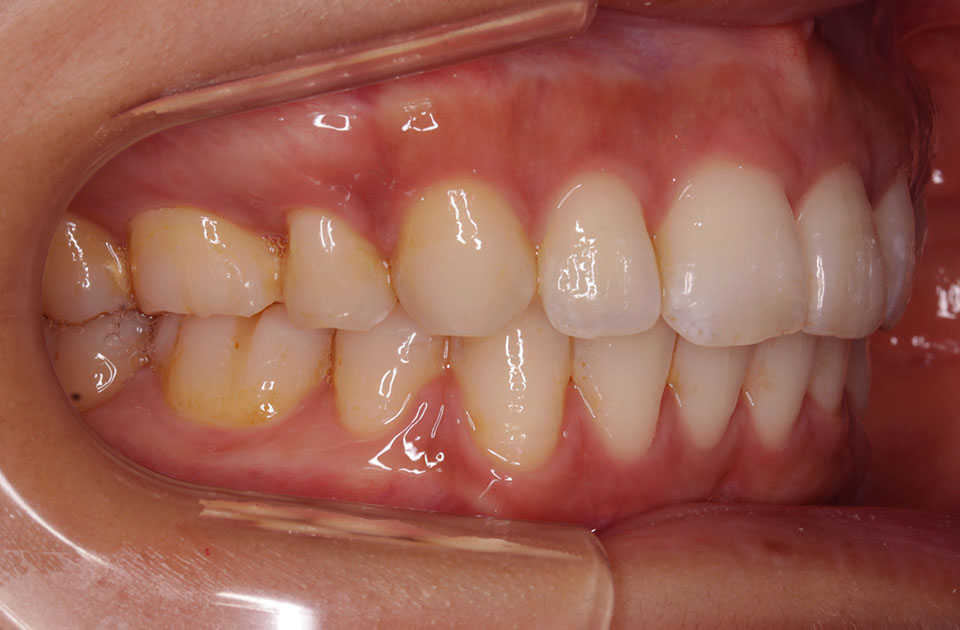

矯正前 右側

矯正後 右側